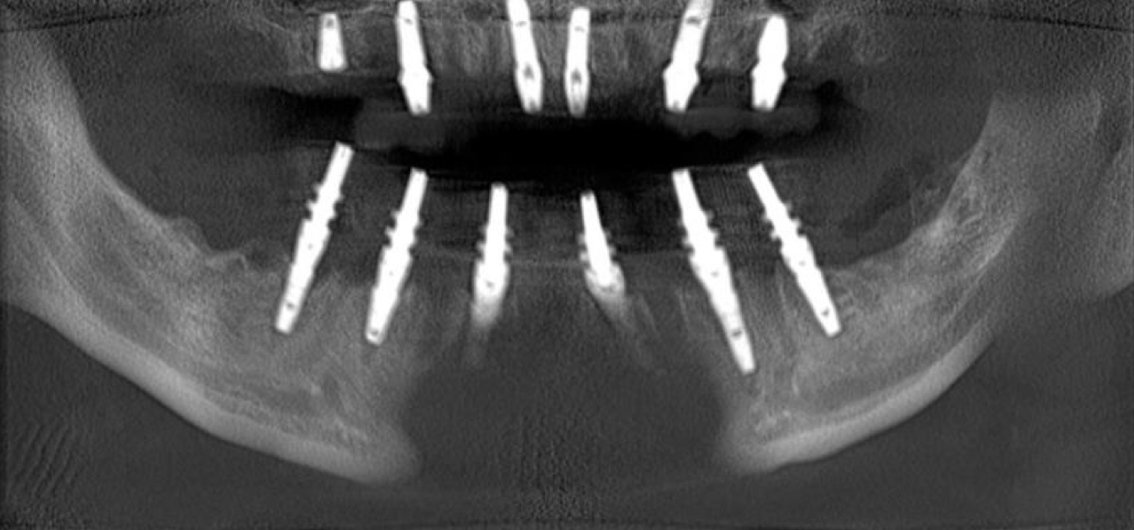

Работа началась с верхней челюсти. Были удалены все зубы, установлено 6 имплантов и сразу зафиксирован временный протез ортопедом.

Заживление проходило комфортно для пациента, по плану.

Далее была проведена та же процедура на нижнюю челюсть и вскоре уже сделаны постоянные коронки.